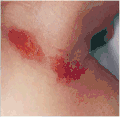

Symptoms of a prior nuchal cord shortly after birth in the baby may include duskiness of face, facial petechia, and bleeding in the whites of the eye.[1] Complications can include meconium, respiratory disease, anemia, and still birth.[1]

Abrasion from a nuchal cord